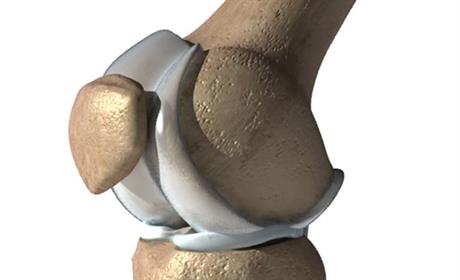

Klinički pregled ortopeda i fizioterapeuta sastoji se od serije testova kojima se isključuju ili potvrđuju specifična oštećenja u i oko koljena

Meniskusi imaju ulogu sekundarne stabilizacije koljena, te pomažu boljem kontaktu zglobne glavice i čašice

No, niti križni ligamenti ne mogu sve sami, a pogotovo ne mogu nositi cijelo tijelo, već služe više kao osigurač pri kretanju